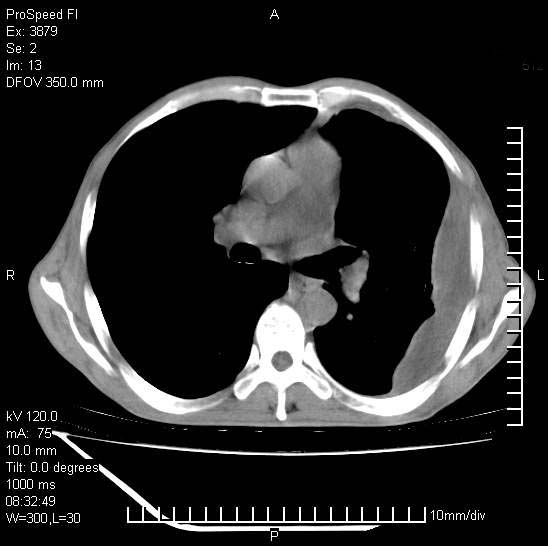

以下是引用37度在2008-6-6 11:20:00的发言:[br]1.包裹性积液,多考虑结核性;[br]2.穿刺术后改变。

以下是引用312nanyang在2008-6-6 15:12:00的发言:[br]基本支持楼主意见[br]疑问?左下肺支气管旁的软组织(16层)密度怎么解释?淋巴结还是斜裂胸膜增厚所致?能否增强进一步检查